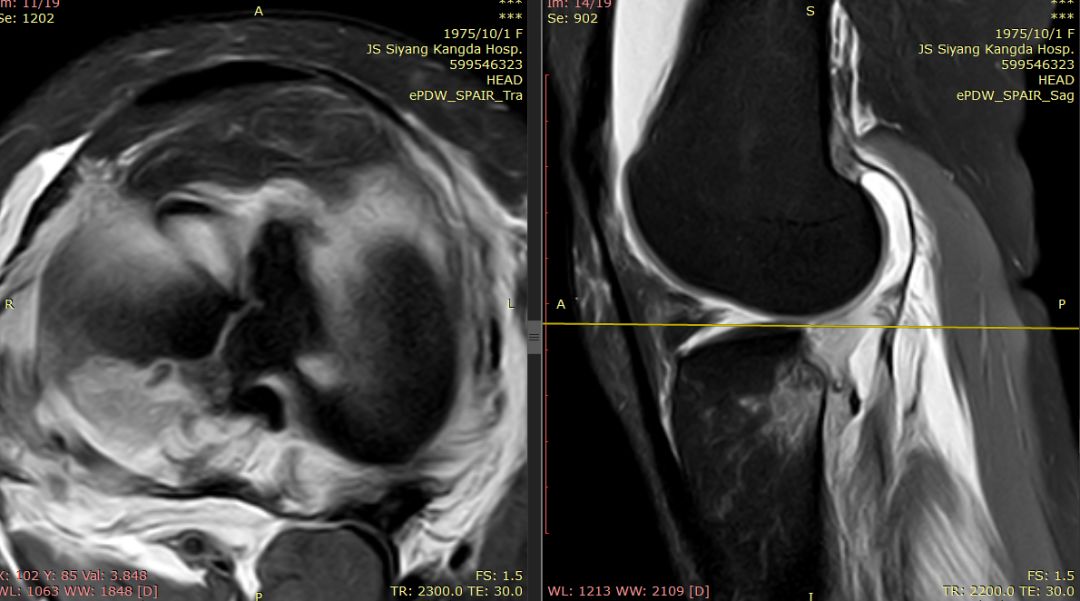

女44岁,外伤

前交叉韧带“消失”

外侧半月板后角“消失”

下图横断面的标线标记的是左下图,为外侧半月板的桶柄样撕裂移位